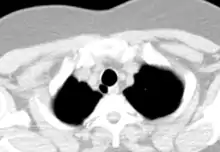

An adult's trachea has an inner diameter of about 1.5 to 2 centimetres (0.59 to 0.79 in) and a length of about 10 to 11 centimetres (3.9 to 4.3 in); wider in males than females.[2] It begins at the bottom of the larynx, and ends at the carina, the point where the trachea branches into left and right main bronchi.[2] The trachea is surrounded by 16 - 20 rings of hyaline cartilage; these 'rings' are 4mm high in the adult, incomplete and C-shaped.[2] Ligaments connect the rings.[3] The trachealis muscle connects the ends of the incomplete rings and runs along the back wall of the trachea.[3]

The trachea begins at the lower edge of the cricoid cartilage of the larynx,[3] and ends at the carina, the point where the trachea branches into left and right main bronchi.[2] The trachea begins level with the sixth cervical vertebra (C6) and the carina is found at the level of the fourth thoracic vertebra (T4),[2] although its position may change with breathing.[3]